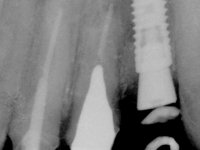

Endodontic treatments were performed and a metalic non screwed intra radicular post was placed on tooth 1.1. An alginate impression was made for laboratory confection of a reinforced acrylic provisional bridge, with teeth 1.1 and 2.2 as abutments and 2.2 as a pontic. After preparation of tooth 1.1 and root preparation of 2.1, the bridge was relined in mouth with self-polymerizable acrylic using a metal post for further retaining the prepared root canal on 2.1. Tooth 2.2 was cut at the gingival level to function as support. In the same session, the impression of the root canal of the 2.1 was made for the laboratory confection of a cast post and core. A double mixture technique with plastic tutor was used after previous canal vaseline with endodontic file and cotton. The provisional bridge was provisionally cemented and the cast post and core was made in the laboratory. Cast post and core cementation was made with resin-reinforced glass ionomer cement and the provisional bridge had to be readjusted to the new situation by removing the post at the site of 2.1. After careful surgical planning, a dental implant was placed, simultaneously with extraction of the root of tooth 2.2. The provisional bridge was placed by resting on the healing screw placed in the implant. The respected osteointegration period was 12 weeks, during which the provisional bridge was relined twice. After complete maturation of hard and soft tissues, definitive impressions were made. The gingival retraction technique was applied with an impregnated retraction cord and impression was performed using double mixture, open tray impression technique. A custom precious metal abutment implant was prepared in the lab, along with 3 metal caps to be used as infrastructures for the metal ceramic crowns. Particular care was taken in the confection of the cervical finishing line of the implant abutment, in order to follow the soft tissues emergence profile. Proof of infrastructures was done in the mouth being evaluated clinically and imagiologically. Collection of color information was done by the ceramist at the office. Ceramic was applied in the laboratory and the finished work was placed in the mouth after approval by the patient. Definitive cementation was made with resin-reinforced glass ionomer cement, and the first crown to be cemented was that of the implant, to facilitate removal of the excess.